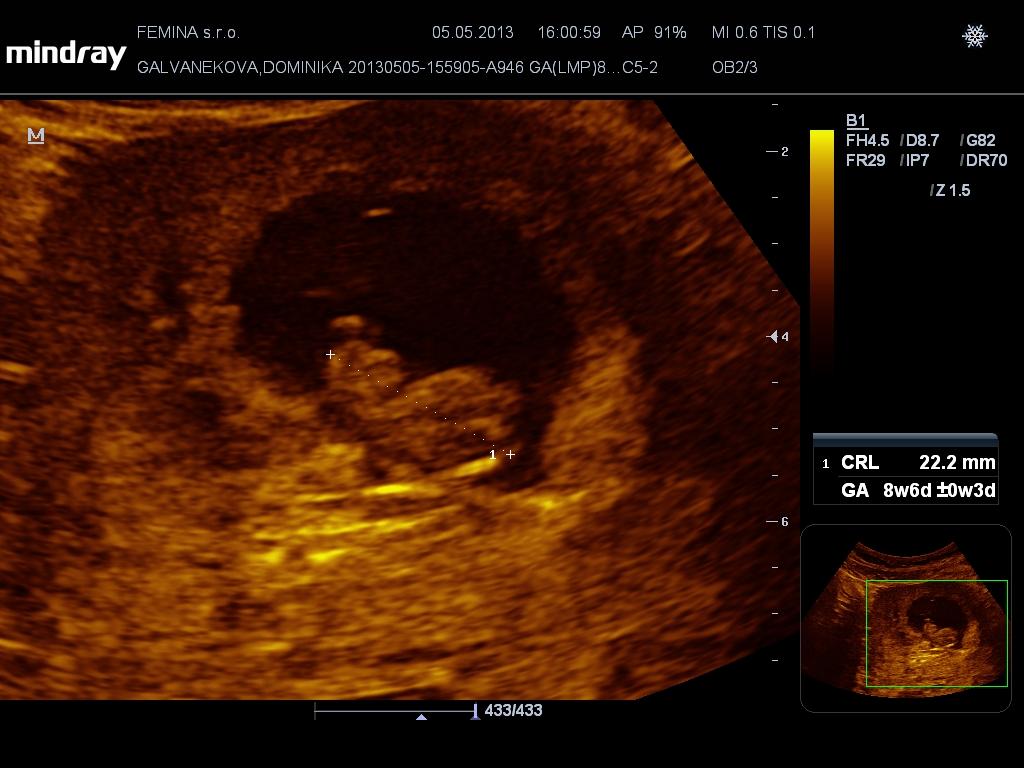

ahojte baby, ozaj ste sa zas rozpisali 🙂 mala som co dohanat 🙂 boli sme vcera na usg a male malo krsne 2,2cm a srdiecko bilo nadherne 😀 pridavam foto 🙂